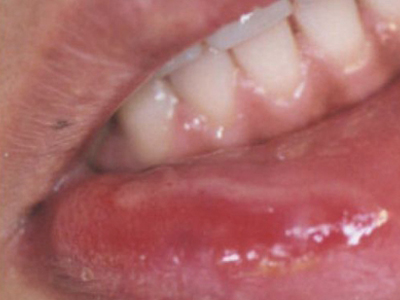

二期口腔梅毒会出现梅毒性黏膜炎及梅毒黏膜斑症状,梅毒性黏膜炎好发于舌、唇黏膜及口角等处,表现为黏膜充血、弥漫性潮红,可有糜烂。舌背有大小不一的光滑区,舌乳头消失。

梅毒黏膜斑是二期梅毒最常见的口腔损害。可发生在口腔黏膜的任何部位,以唇黏膜最多见,其次为软腭、舌背、舌底等部位。损害呈灰白色、光亮而微隆的斑块,圆形或椭圆形,直径约1cm,边界清楚。易发生糜烂或浅表溃疡,表面覆盖灰白色假膜,周围有红晕。黏膜斑常为多个,内含有大量梅毒螺旋体。